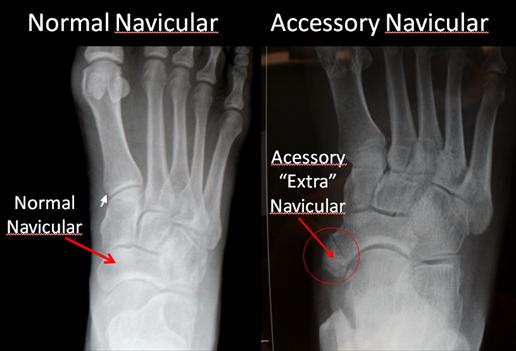

By mile 9 or 10 I felt pleased that I had gone father than ever. I was in the double digits! Unfortunately, with regards to things that are doubled, my bad ankle was beginning to act up. See, I have Accessory Navicular Syndrome, and my extra navicular bone isn't meant to be weight-bearing.

I have 207 bones in my body!